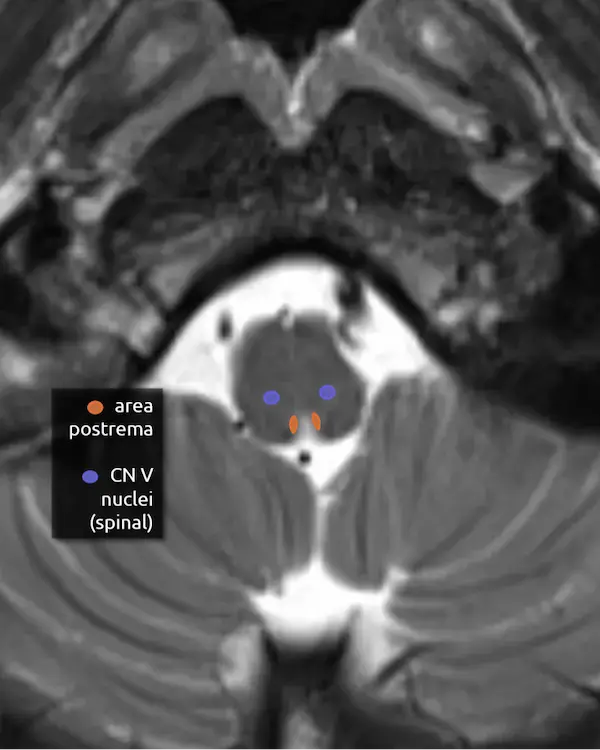

5. Spinal nucleus of the trigeminal nerve (CN V)

6. Area postrema

The area postrema is in the medial dorsal medulla along the floor of the fourth ventricle and median aperture. It is one of several circumventricular organs (CVOs) that do not have a blood-brain barrier. CVOs can be divided into secretory (e.g. secrete hormones) or sensory (e.g. sense hormones and toxins in the CSF). The area postrema is sensory, responsible for detecting toxins and inducing vomiting.

Signal abnormality in the area postrema is a characteristic feature of neuromyelitis optica spectrum disorder (NMOSD). Damage to this area, either in NMOSD or from other conditions, can cause area postrema syndrome, characterized by nausea, vomiting, and sometimes hiccups.